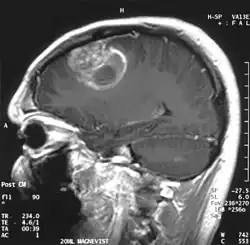

En las imágenes de TC y RM se muestra como una lesión heterogénea, de contorno irregular, que capta contraste en anillo y con un área central necrótica.

Diagnóstico por imagen y glioblastoma

La TC muestra una lesión de morfología irregular, predominantemente hipodensa y fuertemente dishomogénea, debido a la presencia de grandes áreas necróticas de más clara hipodensidad y de áreas sólidas hiperdensas. Estas últimas son la expresión de un rápido crecimiento y por lo tanto de una elevada malignidad. Son frecuentes las zonas hemorrágicas, que van desde pequeños focos a grandes áreas hemáticas que pueden cubrir toda la lesión. Es característica la morfología en "mariposa" si el tumor se asienta en ambos hemisferios a través del cuerpo calloso.

Tras la aplicación de contraste aparecen gruesos anillos alrededor de las áreas necróticas. En la RM, la parte sólida aparece hipointensa en T1 e hiperintensa en T2 con zonas de señal más elevada en las partes de mayor celularidad. Las áreas necróticas, hiperintensas en T2, pueden presentarse hipo-, iso- o hiperintensas en T1 en función del contenido proteico o de productos de la degradación de la hemoglobina. El realce tras el contraste suele ser intenso e irregular en la periferia del tumor e identifica sobre todo la componente celular "proliferativa" de la neoplasia. Son comunes las áreas puntiformes y serpiginosas de ausencia de señal de flujo, asociadas a la presencia de una neovascularización rica. Estos vasos de neoformación patológica carecen de barrera hematoencefálica, lo que explica tanto la abundante impregnación como el edema vasogénico perilesional (véase la sección anterior), debido al paso de líquido al medio extracelular.[72][73]